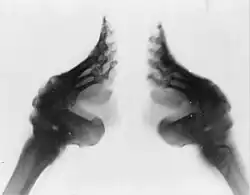

Девочкам ломали кости ступни, после чего полоской ткани привязывали к ступне все пальцы ноги, кроме большого, и заставляли ходить в обуви малого размера, отчего ступни значительно деформировались, иногда лишая возможности ходить в будущем. Такие ноги традиционно назывались «золотыми лотосами». От размера ступни зависел престиж невесты, к тому же считалось, что принадлежащей к высокому обществу даме не следует ходить самостоятельно. Это бессилие, неспособность к передвижению без посторонней помощи составляло, по литературным свидетельствам, одну из привлекательных черт женщины-аристократки: здоровые и недеформированные ноги ассоциировались с крестьянским трудом и «подлым происхождением».

Идеальная нога должна была не превышать 7 сантиметров в длину; такие ноги назывались «золотые лотосы»[9]. Стопа длиной в 10 см носила название «серебряный лотос», если же длина превышала 10 см — «железный лотос» и не сильно котировалась. Стопа не должна была выглядеть как опора для тела[3].

Самой распространённой проблемой было возникновение инфекций ног. Несмотря на то что ногти регулярно подстригали, они часто врастали в палец, вызывая воспаление и повреждая ткани пальца. По этой причине иногда ногти удалялись. Также несколько слоёв плотной ткани не пропускали воздух к стопе[18], и из-за слишком тугой повязки кровообращение в стопе нарушалось, а кровообращение в пальцах ног вообще исчезало. В результате инфекционные процессы в пальцах не прекращались; начинался некроз тканей. Если инфекция переходила на кости, то пальцы могли отпасть, это считалось благоприятным, поскольку теперь ногу можно было перебинтовать ещё туже. Если у девочки были более широкие стопы, в них иногда втыкали осколки стекла или черепицы, для того чтобы спровоцировать инфекцию и, как следствие, некроз тканей. Инфекция ноги могла привести к смерти от заражения крови, если же девочка выживала, то во взрослом возрасте у неё чаще возникали различные заболевания. В начале процесса значительная часть костей стопы оставалась сломанной часто на несколько лет. Когда девочка становилась старше, кости начинали срастаться. Однако даже после того, как кости срастались, они оставались хрупкими и часто снова ломались, особенно в подростковом возрасте, когда были ещё недостаточно крепкими. Взрослые женщины часто страдали от переломов ног и бедренных костей, поскольку в положении стоя им было трудно сохранять равновесие, а также трудно вставать из сидячего положения[21]. В 1997 группа исследователей провела сравнение между пожилыми женщинами с деформированными и здоровыми ногами. Было выяснено, что те женщины, чьи ноги были деформированы, чаще страдают от остеопороза (масса костной ткани в бедренных костях у них была ниже на 5,1 %, а в позвоночнике — на 4,7 %), что означает повышенный риск перелома костей. При этом риск падения у них вдвое выше (38 % против 19 %)[3].